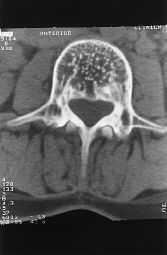

Las radiografíasrealizadas en el húmero muestran (fig. 1A) un desplazamientode la cavidad medular e imágenes radiolucentes con aumentode densidad, al tiempo que hay pérdida de la corticalnormal. En la tomografía axial computadorizada (TAC) (fig.1B) se puede apreciar rarefacción en parches de huesostubulares con atrofia interna y agrandamiento de la corteza. Laslesiones descalcificadas revelan un margen bien definidoesclerótico con una superficie interna densa y unasuperficie externa que evoluciona gradualmente a hueso normal. Elresto del hueso muestra una apariencia normal.

Figura1B.